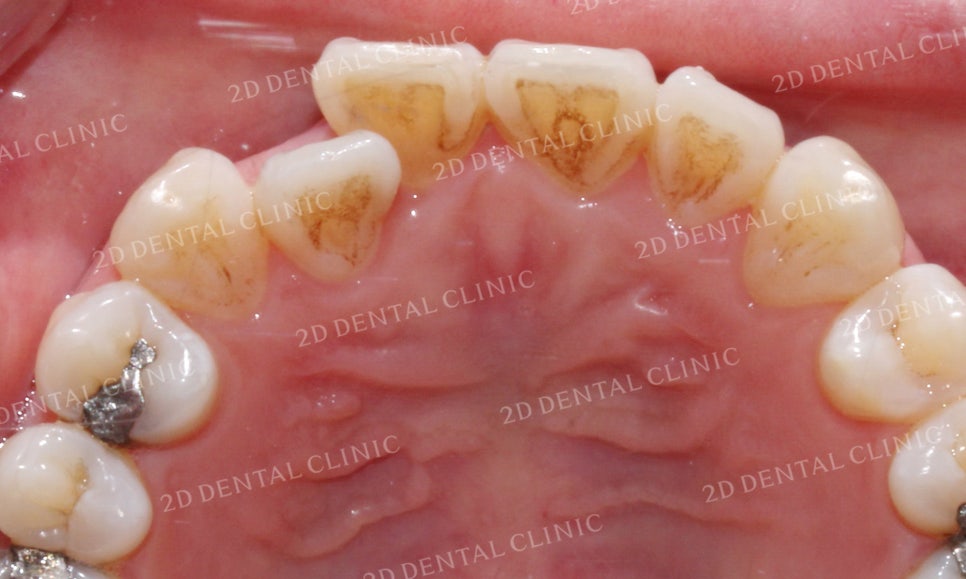

상악의 설측면 사진을 보시면

전치부의 치열이 상당히 조화롭지 못한 것을

확인할 수 있습니다.

환자분의 경우 부정교합 증상이 발견되기 때문에

전체교정으로 치아 교합 상태를 바로잡고

치열을 가다듬는 치료 계획을 추천드렸으나

반대교합 증상이 있는 전치부의 치아만을

부분교정으로 진행하시게 되었습니다.

따라서 본 교정 Case는 치아의 전체교정이 아닌

부분교정 과정을 거쳤음을 감안하시고 읽어주시기 바랍니다.